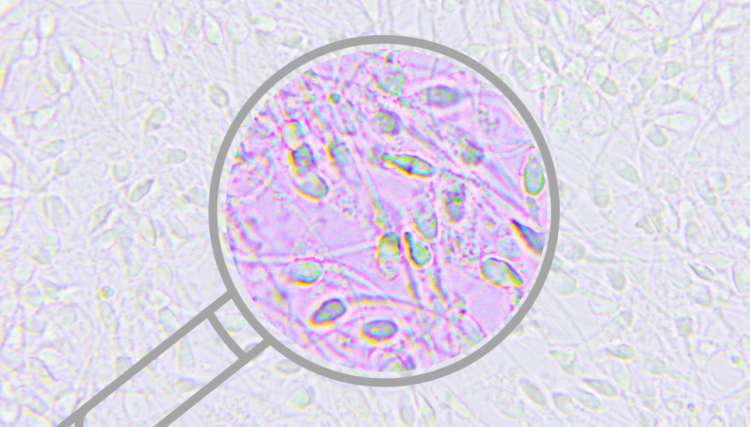

Jak interpretować wyniki badania nasienia